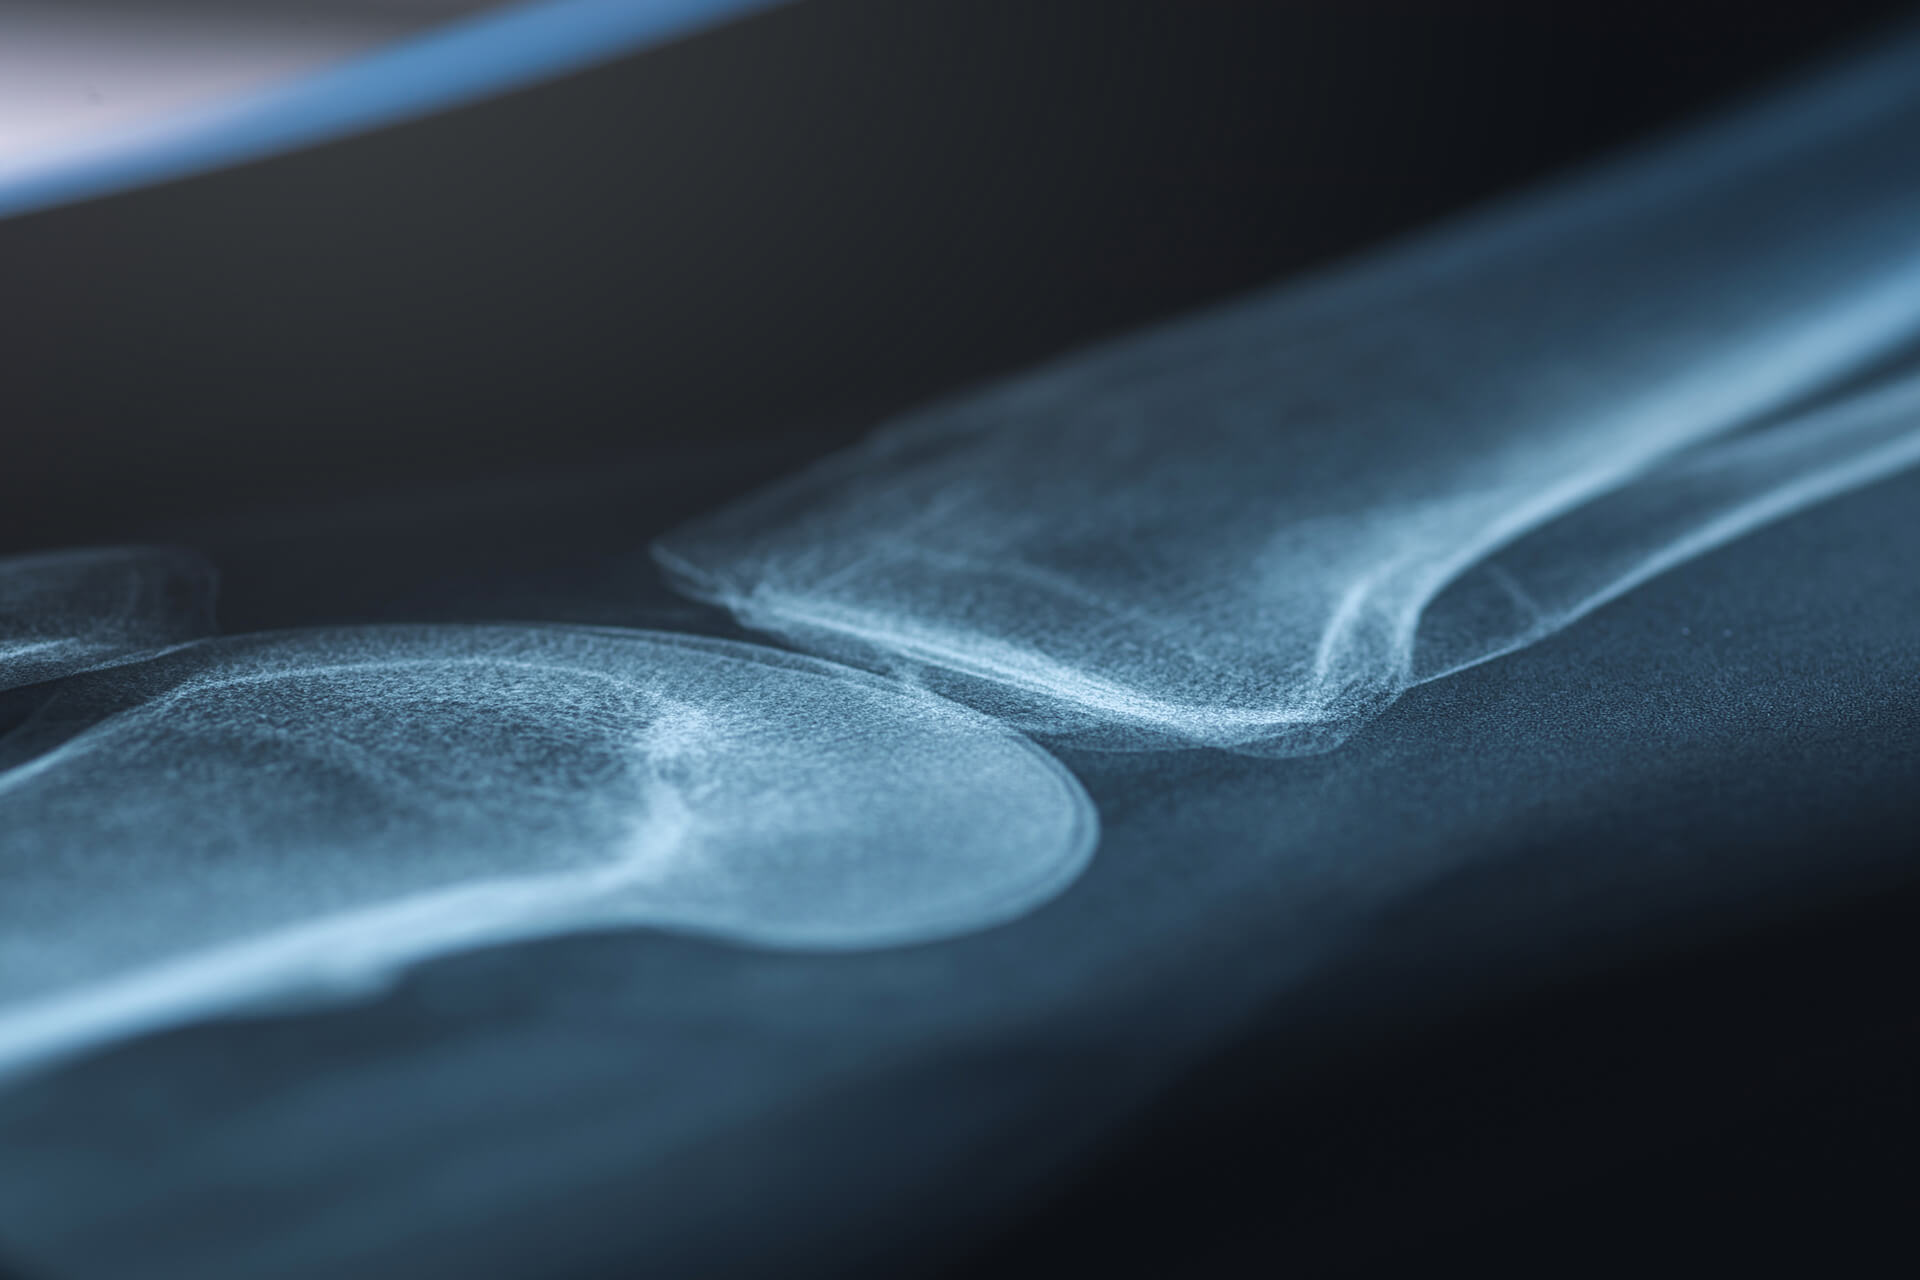

partial knee replacement singapore

A partial knee replacement targets only the damaged part of the joint, helping preserve healthy bone and ligaments while restoring smoother movement and reducing pain.